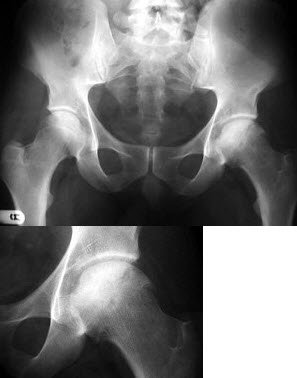

173、单项选择题

女,60岁,髋部疼痛、活动受限、跛行,结合图像,最可能的诊断是()

A.骨岛

B.髋关节结核

C.股骨头缺血坏死

D.退变性囊肿

E.暂时性骨质疏松